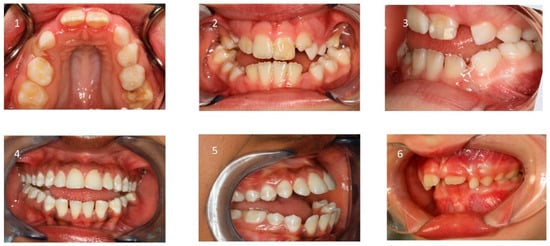

Underlying these functional consequences, increased airway resistance, mainly caused by adenoidal hypertrophy, has been associated with craniofacial disharmony and malocclusion, as demonstrated by Linder-Aronson [57]. Mouth breathing has a multifactorial etiology, often stemming from anatomical obstructions such as adenotonsillar hypertrophy, midfacial hypoplasia, enlarged turbinates, or a deviated nasal septum. In some cases, it may also result from neuromuscular hypotonia or persist as a habitual pattern after treatment of anatomical obstructions (Figure 1).

The soft tissue stretch theory, proposed by Solow and Kreiborg [68], postulates that mouth breathing alters head posture and muscle recruitment, thereby negatively affecting craniofacial growth. Mouth-breathing children often exhibit features collectively referred to as “adenoid facies” or long-face syndrome, along with reduced orofacial muscle tone [57,61,69,70,71]. A low tongue position is most often a result of mouth breathing (Figure 2).

This results in insufficient internal tongue pressure on the palate and a predominant cheek pressure, leading to a reduction in transverse growth of the maxilla and the development of a high-arched palate and lateral crossbites [72].

5.2. Intraoral Findings

Malocclusion is highly prevalent in children with OSA. They often present posterior crossbites in addition to lateral functional shifts due to a narrow maxilla [84,85,86]. Regarding the palatal vault, it is higher and narrower than in non-affected children [87]. This is related to the altered equilibrium between the tongue and cheeks [72]. In addition, an anterior open bite and sometimes a deep bite, an increased overjet due to a retrognathic mandible, protruded upper incisors, and crowding in the maxilla and the mandible are constant findings [69,88,89].

Furthermore, ankyloglossia and reduced tongue mobility may be present [90,91,92,93]. (Figure 5 and Table 2).